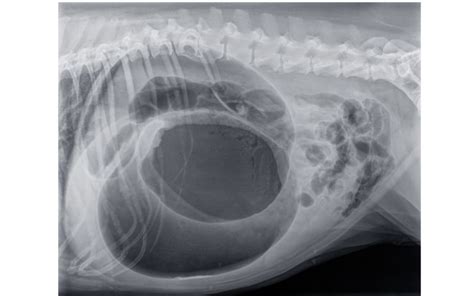

Veľmi obávanou chorobou je torzo žalúdku, pri ktorom dochádza u psa k pretočeniu žalúdka. Torzo môže byť pre psa smrteľné, ak sa včas nevyhľadá lekárska pomoc. Je dôležité zdôrazniť, že ak má pes bolesti brucha, mal by byť okamžite vyšetrený veterinárnym lekárom.